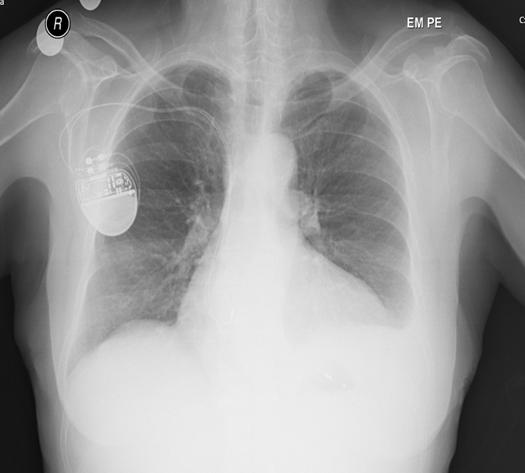

Arco da Aorta à Direita e Roubo de Fluxo Arterial: Relato de Caso

Luciana Yukie Nakagawa, Ana Caroline de Mélo Viana, Maria de Fatima de Lira Silva, Adriene Gonçalves Mota, Renan de Lima Rocha, Marcelo Calil Burihan, Renata Nunes da Silva

bjcr113